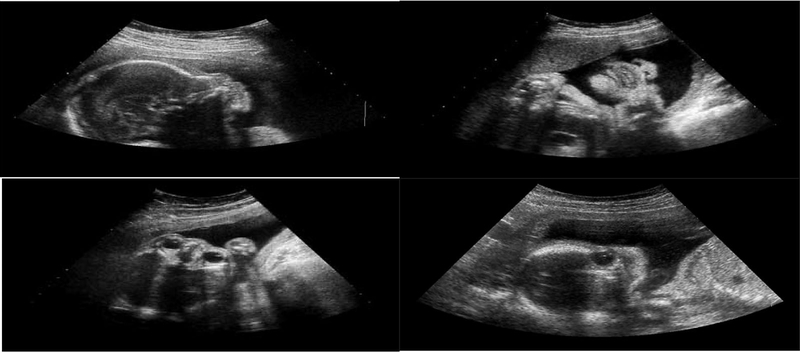

Tuần thứ 11 - 13: Kiểm tra dị tật thai nhi

Vào tuần thai thứ 11 đến 13 tuần 6 ngày, những dị tật bộc lộ bên ngoài cơ thể thai nhi đã có thể nhìn vào rõ khi thực hiện siêu âm. Đây chính là thời điểm mẹ nên kịp thời đến bệnh viện để kiểm tra xem thai có đang phát triển bình thường hay không.

Bác sĩ chuyên khoa sẽ giúp mẹ đo tim thai, đánh giá những chi đang lớn dần của con cũng như cơ hoành.

Một trong những bệnh dễ xác định tại thời điểm này là bệnh Down thông qua độ mờ da gáy. Khi siêu âm bác sĩ sẽ báo cáo cho mẹ nếu kết quả đo độ mờ da gáy thất thường.

Những mốc siêu âm quan trọng mà mẹ bầu cần nhớ 2 Giai đoạn này bác sĩ có thể phát hiện thai dị tật thông qua siêu âm